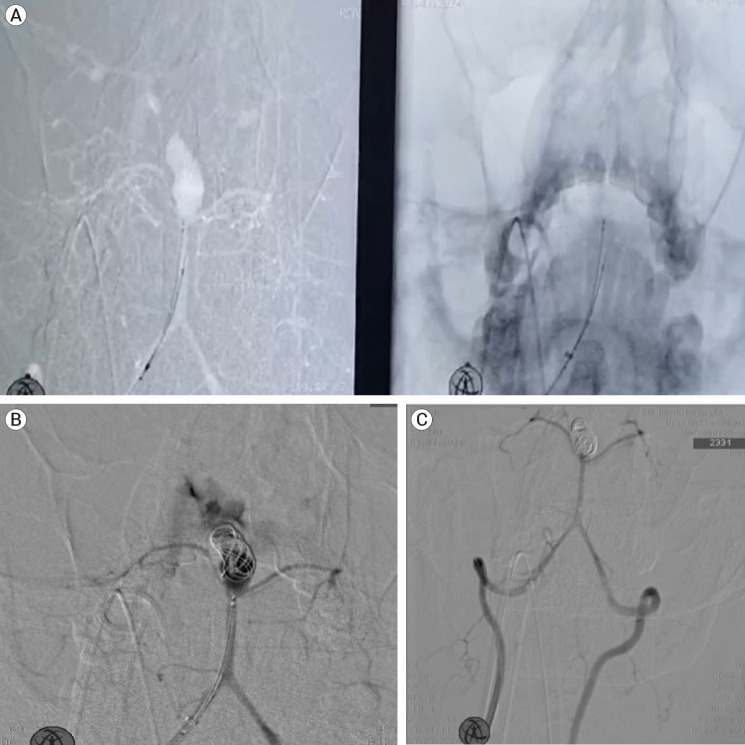

Fahr病是一种罕见的疾病,其特征是认知、精神和运动功能逐渐下降,与基底节区特发性钙化有关,通常以常染色体显性方式遗传。急性表现通常为癫痫发作;然而,我们提出了一个病例的急性表现,其中恶化的原因是动脉瘤性蛛网膜下腔出血。Fahr病与颅内动脉瘤之间的关联极为罕见,迄今为止文献记载的病例只有5例。本报告是第六次这样的案例。此外,所有先前报道的动脉瘤都局限于前循环;因此,这是第一例以后循环动脉瘤为表现的Fahr病。本病例以严重头痛主诉送急诊。头部CT显示双侧基底节区钙化及蛛网膜下腔出血。数字减影血管造影(DSA)显示颅底尖端动脉瘤。动脉瘤采用Neqstent辅助盘绕术治疗。术中动脉瘤出血发生在置入第一圈后。肝素被逆转,血压下降,动脉瘤被进一步的线圈包裹,直到出血停止。采用脑室外引流术治疗蛛网膜下腔出血和脑室内出血。Fahr病的确切机制尚不完全清楚,但据信它在由血管中的矿物质沉积引起的动脉瘤的发展中起作用。对于出现不明原因的反复发作的意识丧失的患者,即使他们已经诊断为Fahr病,也应进行脑计算机断层血管造影(CTA)以排除动脉瘤,以防止将这些发作错误地归因于癫痫。此外,对于伴有Fahr病或血管炎的动脉瘤,术前应进行血管壁磁共振成像(MRI)检查,以改善治疗计划。

Fahr's disease is an uncommon condition characterized by a gradual decline in cognitive, psychiatric, and motor functions, linked to idiopathic calcification in the basal ganglia, typically inherited in an autosomal dominant fashion. Acute presentation is most often as a seizure disorder; however, we present a case of an acute presentation in which the cause of the deterioration was an aneurysmal subarachnoid haemorrhage. The association between Fahr's disease and intracranial aneurysms is exceedingly rare, with only five cases documented in the literature to date. This report represents the sixth such case. Furthermore, all previously reported aneurysms were confined to the anterior circulation; thus, this is the first documented instance of Fahr's disease presenting with an aneurysm in the posterior circulation. The case here presented to the emergency service with the complaint of severe headache. Computed tomography (CT) of the head showed bilateral basal ganglia calcification and subarachnoid haemorrhage. Digital subtraction angiography (DSA) revealed a basilar tip aneurysm. The aneurysm was treated with Neqstent assisted coiling via jailing technique. Intraoperative aneurysmal haemorrhage occurred just after inserting the first coil. Heparin was reversed, blood pressure decreased and aneurysm was packed with further coils till the bleeding stopped. External ventricular drainage was performed to address subarachnoid hemorrhage (SAH) and intraventricular hemorrhage. The exact mechanisms underlying Fahr's disease are not fully understood, but it is believed to play a role in the development of aneurysms due to mineral deposits in blood vessels. For patients experiencing unexplained recurrent episodes of loss of consciousness, brain computed tomography angiography (CTA) should be performed to rule out an aneurysm, even if they have a known diagnosis of Fahr's disease, to prevent misattributing these episodes to epilepsy. Additionally, vessel wall magnetic resonance imaging (MRI) should be conducted preoperatively in cases of aneurysms linked to Fahr's disease or vasculitis to improve management planning.